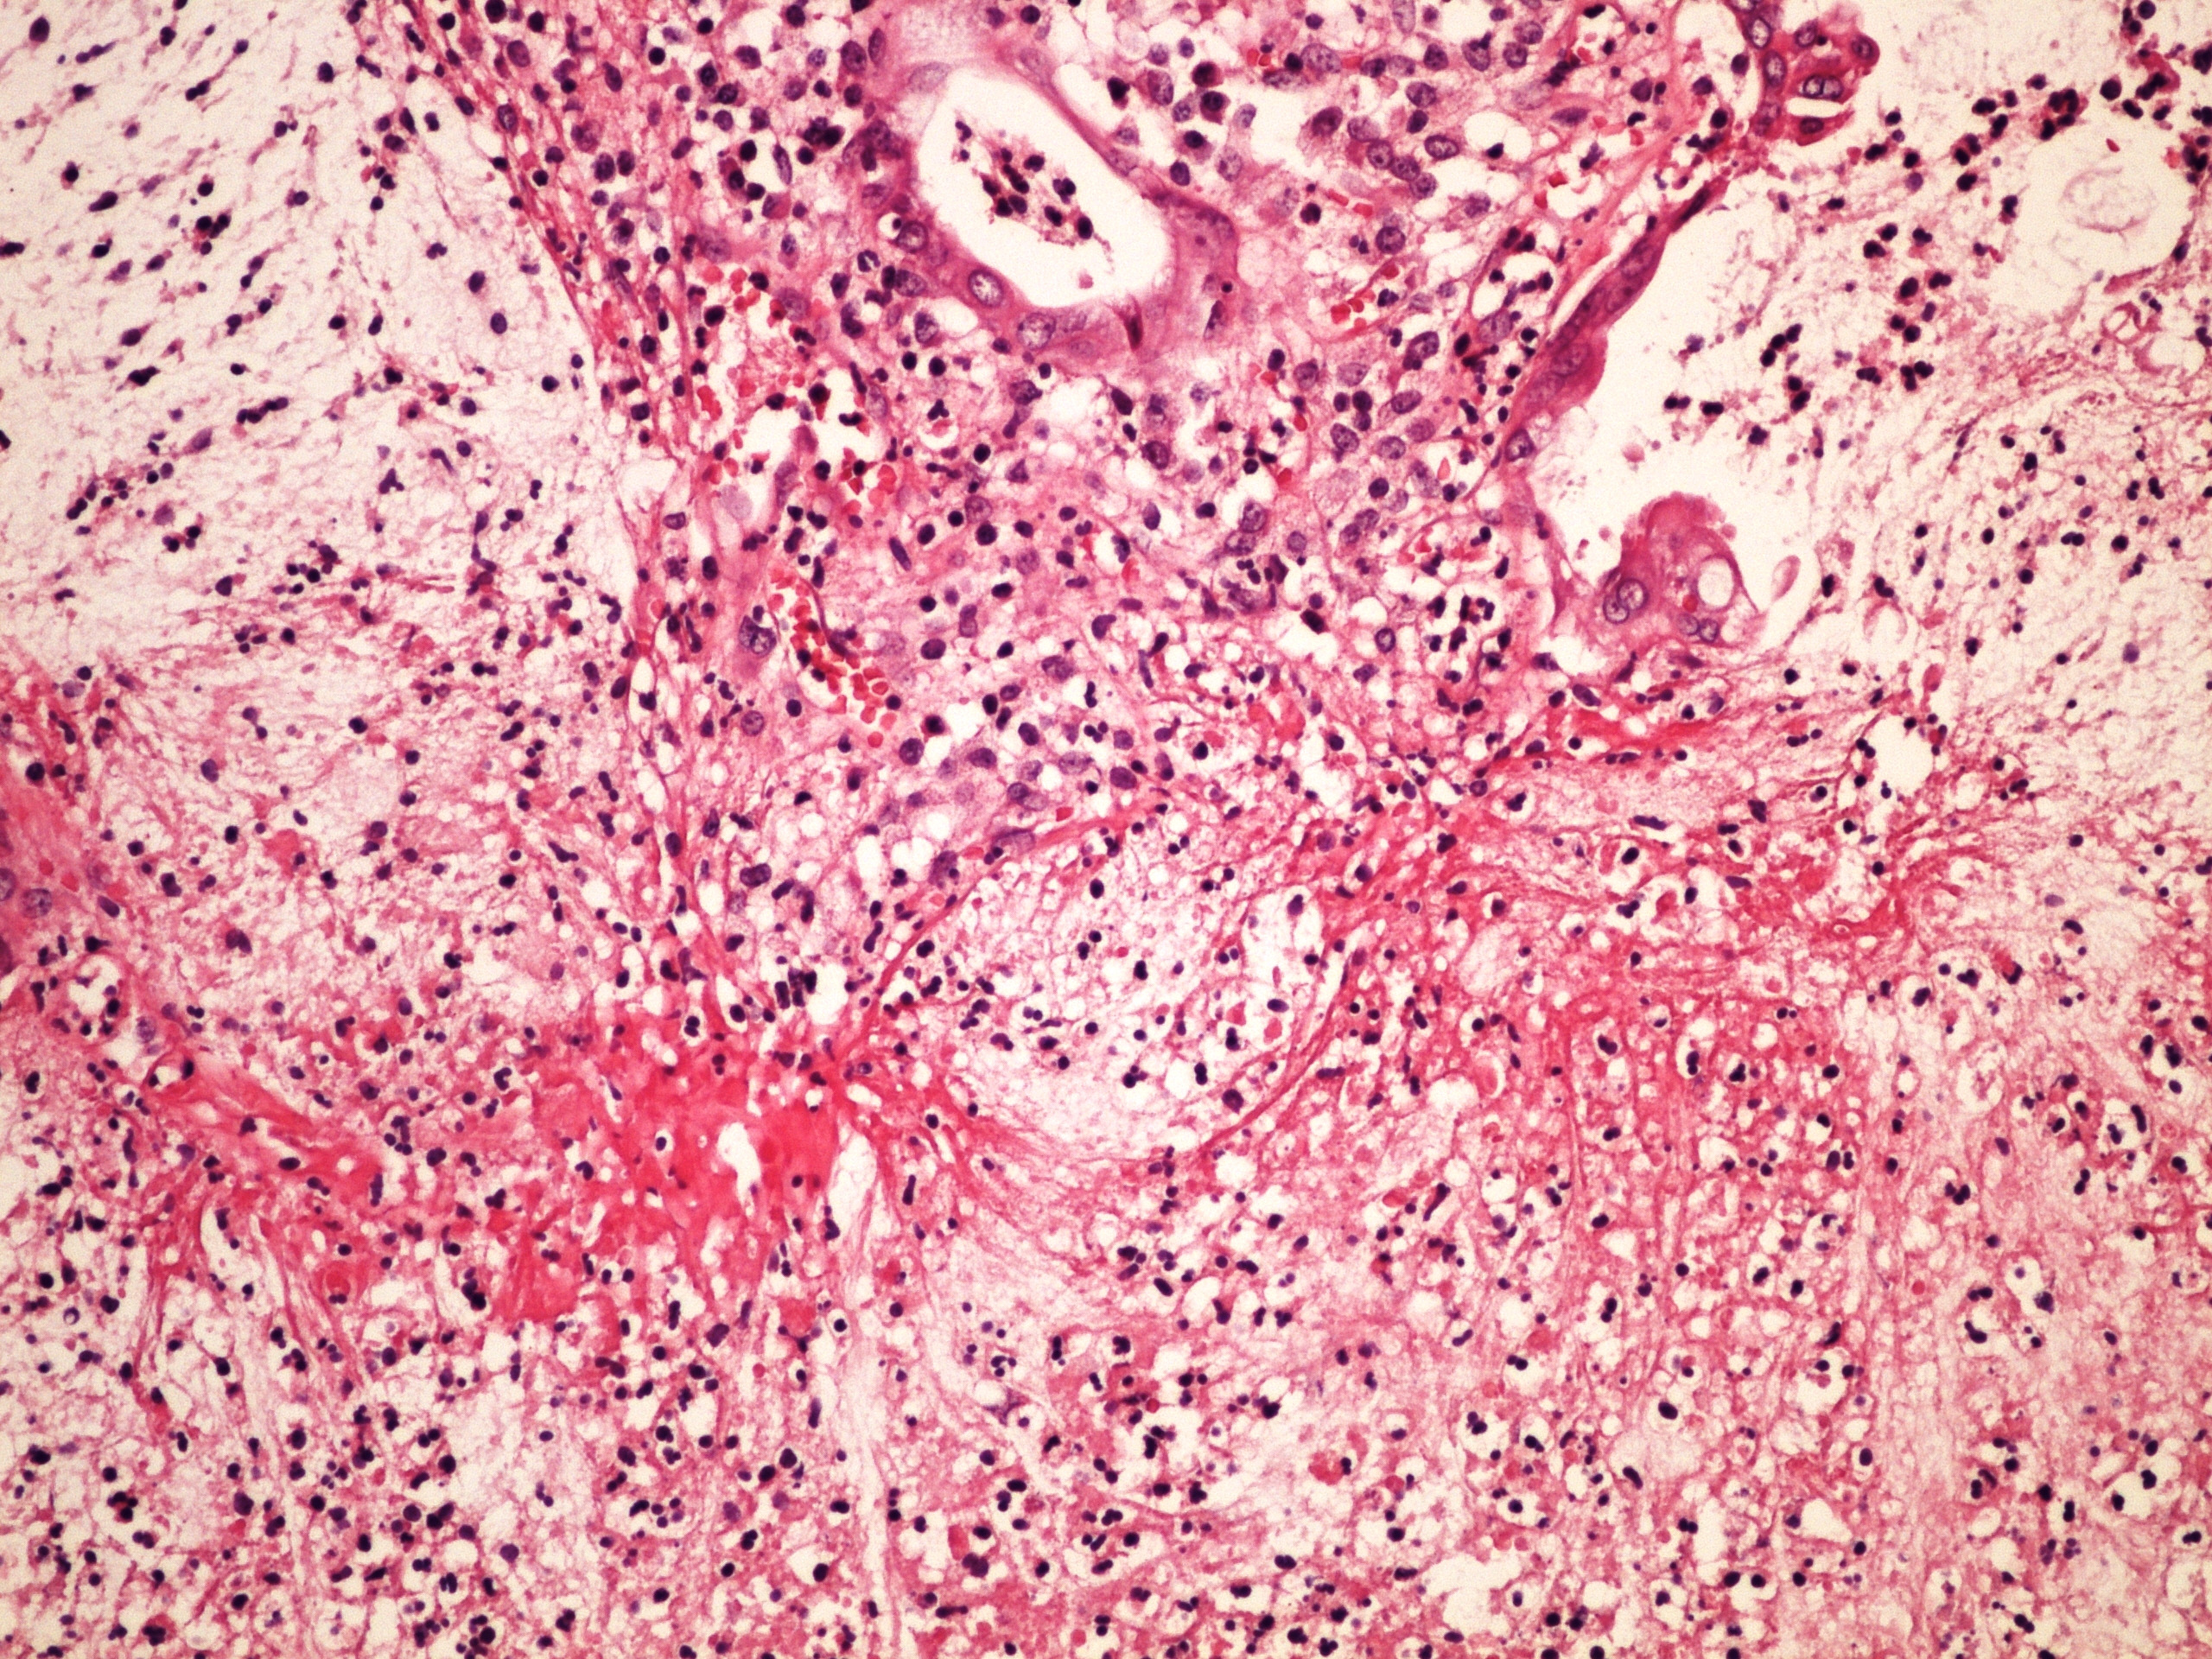

Preparát č.19 a č.20 - obrovskobuněčný granulom

Struktury

- cizorodý světlolomný materiál

- obrovské vícejaderné buňky